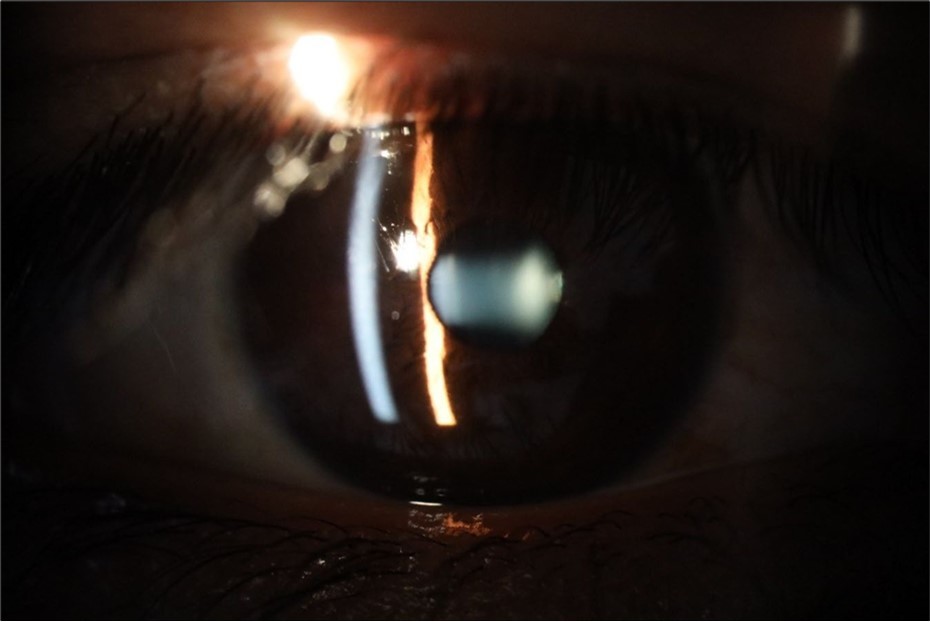

Figure 6.Slit-lamp examination showed a solution of continuity in the left temporal region, which fortunately only affected the conjunctiva and Tenon's capsule, while the sclera was unscathed.

Figure 16.The anterior segment of the right eye shows the vitreous with greater transparency. The cornea and lens, as well as the anterior chamber, are in good condition.

Figure 21.The anterior segment of the right eye responds with difficulty to mydriatics, which is usual in diseased eyes.

Figure 26.The macrograph of the anterior segment of the right eye (affected) shows very good transparency of the cornea, anterior chamber, lens, and vitreous.